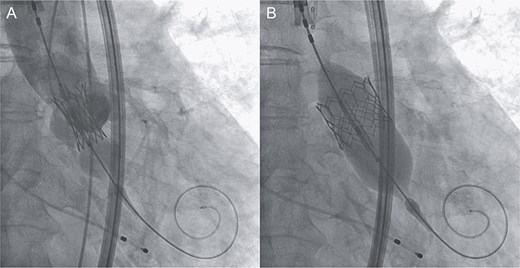

An 88-year-old woman with severe symptomatic AS (aortic valve area: 0.40 cm2; peak velocity: 4.9 m/s; mean pressure gradient: 56 mm Hg) and ischemic heart disease with severe stenosis in the proximal segments of both the left anterior descending (LAD) coronary artery and circumflex arteries was referred from another hospital for invasive treatment. The patient was taking edoxaban 30 mg, nifedipine 20 mg, perindopril 4 mg, and candesartan 8 mg for the treatment of atrial fibrillation and hypertension. The patient’s perioperative risk was high, with a Society of Thoracic Surgeon (STS) score of 9.31% and Logistic EuroSCORE of 23.11%. Following discussion with the heart team, we decided to perform TAVI before coronary revascularization, with percutaneous coronary intervention (PCI) planned postoperatively. We evaluated the aortic valve complex using contrast-enhanced computed tomography (CT), which revealed a narrow sinotubular junction (STJ) with small calcifications measuring 20.6 × 22.3 mm (Fig. 1). TAVI was performed via a transfemoral approach under local anesthesia and sedation. A 23-mm SAPIEN 3 THV (Edwards Lifesciences, Irvine, CA, USA), which provides better coronary access due to its shorter frame length and relatively larger cell size, was deployed without prior balloon aortic valvuloplasty. To minimize the risk of injury to the STJ, the THV was deployed with a reduced balloon volume (−1 cc), and post-dilatation was conducted with the balloon positioned toward the left ventricular side (Fig. 2). Postoperatively, the patient’s blood pressure stabilized with rest and a reduced-sodium diet, allowing modification of the antihypertensive therapy to sacubitril/valsartan 100 mg alone. Additionally, aspirin 100 mg was added to ongoing edoxaban therapy for the planned PCI. The postoperative course was uneventful, and the patient was subsequently discharged. However, on day 4 after discharge, the patient experienced acute chest discomfort. Blood tests, electrocardiography, and transthoracic echocardiography revealed no significant changes from the time of discharge, and the patient was sent home as the symptoms gradually improved. On day 7 after discharge, contrast-enhanced CT—originally scheduled as a preoperative assessment for PCI at the referring hospital— incidentally revealed a localized dissection of the ascending aorta. The entry point of the dissection was located at the STJ extending toward the THV stent frame, consistent with Stanford AAD associated with TAVI (Fig. 3). The patient was transferred to our hospital and underwent surgery, including aortic valve replacement, ascending aorta replacement, and coronary artery bypass grafting (left internal thoracic artery to the LAD and saphenous vein graft to the obtuse marginal branch). Intraoperatively, removal of the THV and calcified STJ tissue revealed a pinhole-like intimal defect, which was continuous with a hematoma within the media and identified as the entry point of the dissection. Macroscopic pathological examination of the resected ascending aorta also confirmed the presence of a small intimal defect (Fig. 4). This intimal injury was therefore considered to have resulted from compression of the calcified tissue caused by THV implantation. After ~1 month of rehabilitation, the patient was discharged in an ambulatory state on postoperative day 30.

Intraprocedural angiographic images show THV implantation performed with a reduced pressure of −1 cc (A) and post-dilatation conducted with the balloon positioned toward the left ventricular side (B).